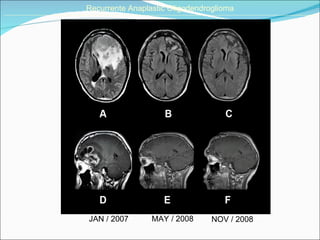

JAN / 2007 MAY / 2008 Recurrente Anaplastic Oligodendroglioma ______________________________________________________________________________________________________________________________________ NOV / 2008

Disease-free survival (6 months) ______________________________________________________________________________________________________________________________________ The median PFS rate was 48.2% for patients with GBM, 60% for patients with AA, and 66.6% for patients with AO.

JAN / 2007MAY / 2008 Recurrente Anaplastic Oligodendroglioma ______________________________________________________________________________________________________________________________________ NOV / 2008

Disease-free survival (6months) ______________________________________________________________________________________________________________________________________ The median PFS rate was 48.2% for patients with GBM, 60% for patients with AA, and 66.6% for patients with AO.